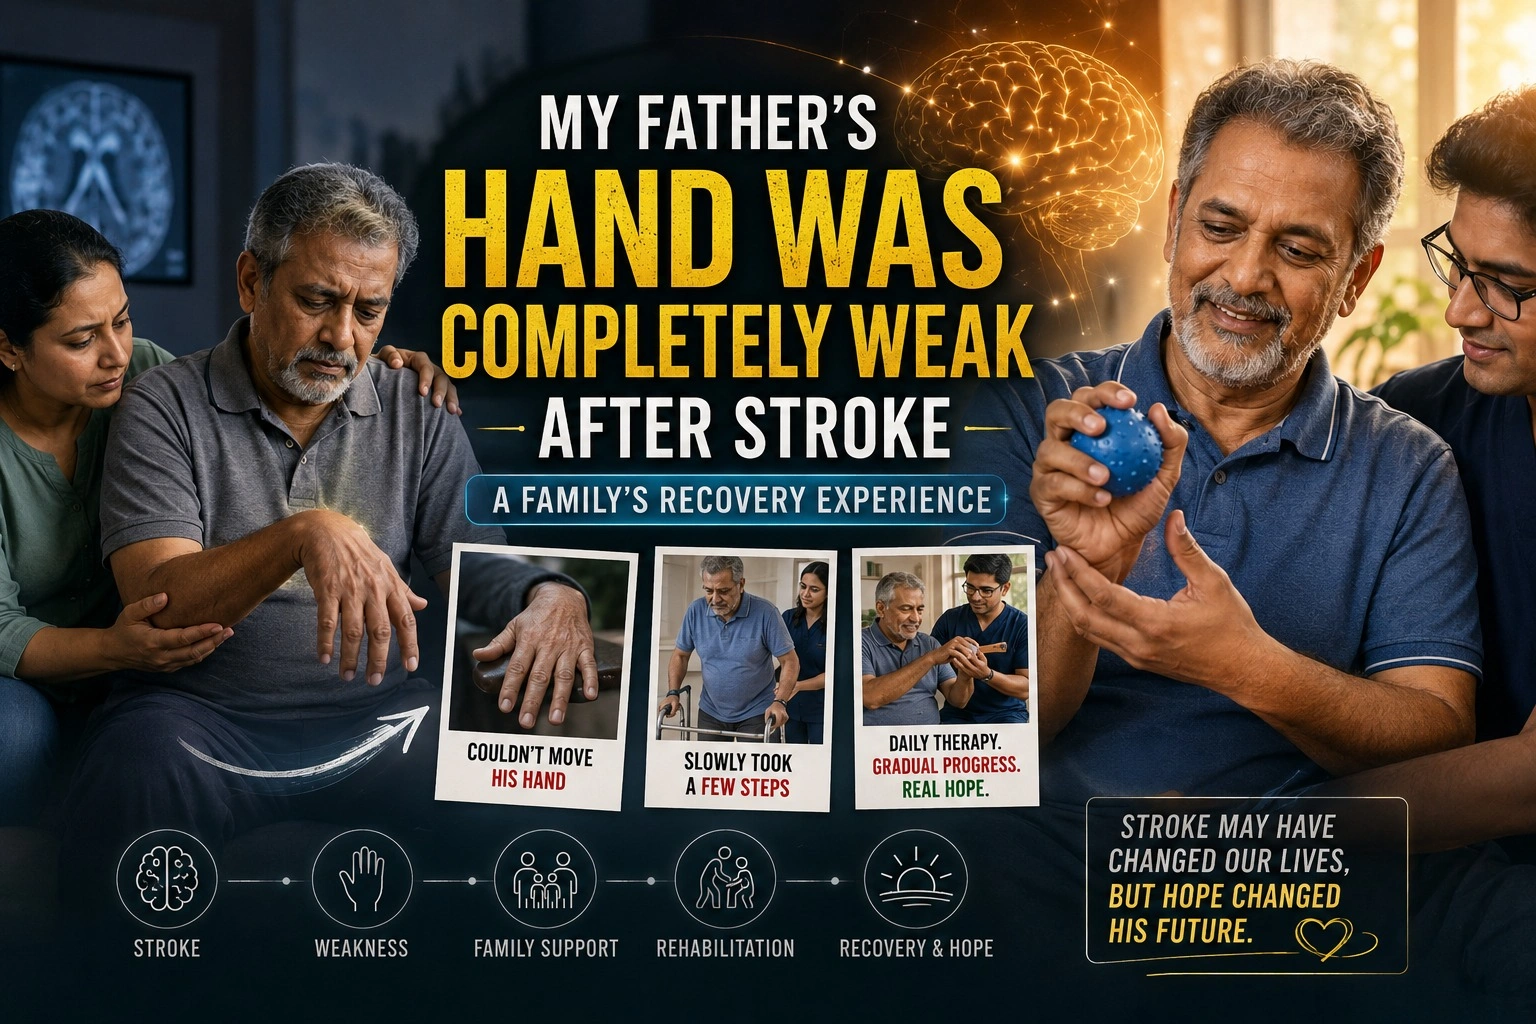

My Father’s Hand Was Completely Weak After Stroke – A Family’s Recovery Experience

???My Father???s Hand Was Completely Weak After Stroke??? – A Family???s Recovery Experience When my…